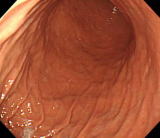

胃の内視鏡

| 胃内視鏡写真 |

左は胃の入口(噴門)から見た胃の中です。胃体部にあるヒダが見えています。

中央は胃角部を見ています。奥に見える黒いものは内視鏡です。

右は胃前庭部です。奥に見える黒い点は幽門です。 |